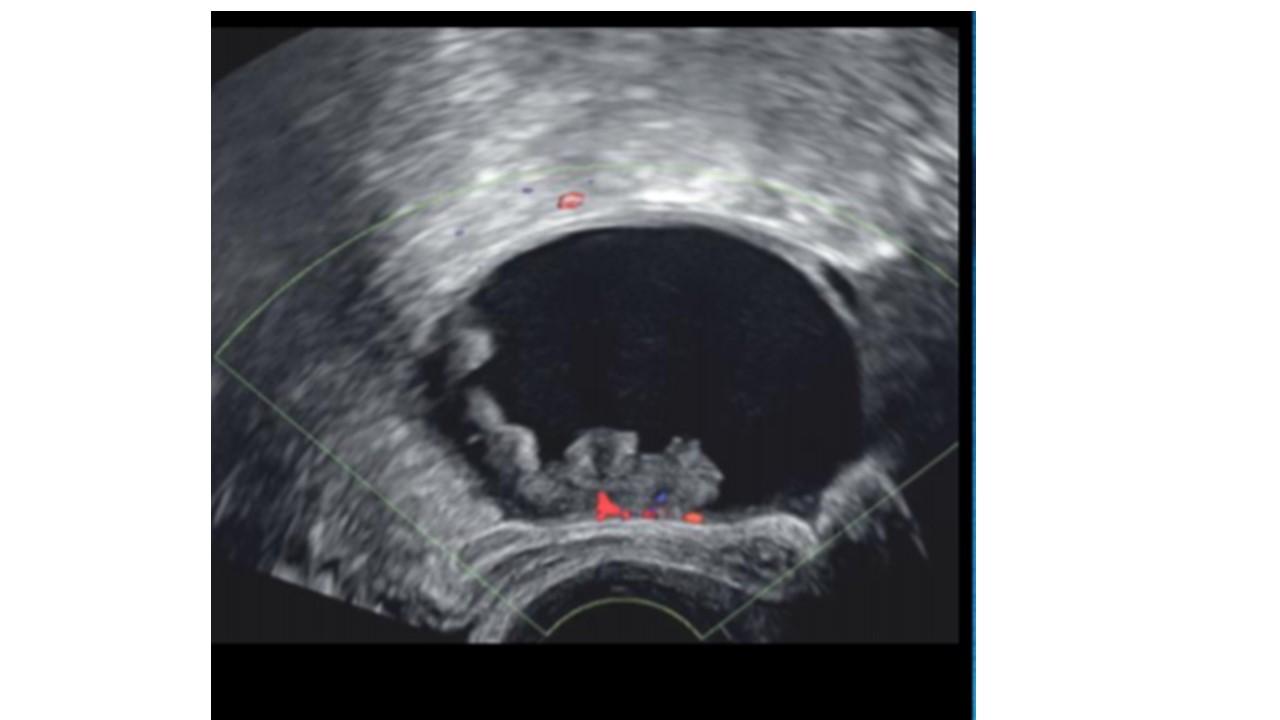

Loupes Cuir Chevelu Echographie. la loupe, ou kyste trichilemmal, est une tumeur bénigne fréquente du cuir chevelu. les loupes du cuir chevelu sont des boules sous le cuir chevelu qui peuvent être gênantes et entraîner la chute des cheveux. aussi appelée loupe du cuir chevelu ou encore kyste pilaire, le kyste trichilemmal est un kyste dermique qui se. La chirurgie de la loupe permet de s'en débarrasser définitivement sous anesthésie locale. Découvrez comment les retirer facilement et rapidement au cabinet avec le chirurgien dermatologue. une loupe est un kyste bénin qui se forme sous le cuir chevelu, souvent invisible sous une épaisse crinière. Découvrez les causes, les risques et les soins postopératoires de cette intervention. • echographie le plus souvent réalisée en première intention • avantages : Pour l'enlever, il faut consulter un dermatologue qui peut l'inciser ou l'exériser selon la taille et la localisation de la loupe. la loupe du cuir chevelu est une tumeur bénigne qui se développe à partir des cellules du follicule pileux.